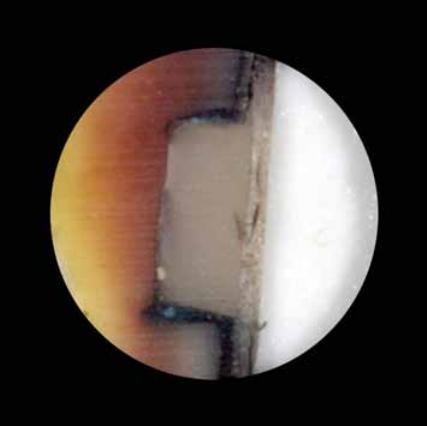

avaliada está na figura 4.

Figura 4 – Exemplo de imagem avaliada no teste de microinfiltração.